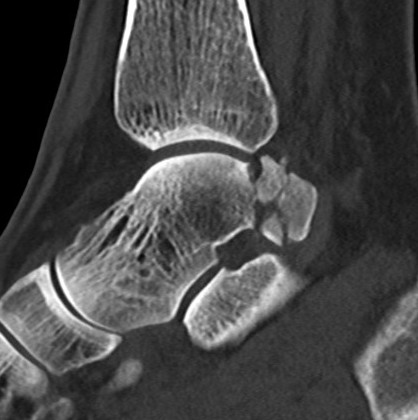

Congruent reduction

Posterior process fracture talus after medial subtalar dislocation

CT post reduction

Ensure

- congruent reduction

- look for fractures of talus / calcaneum

- look for intra-articular fragments